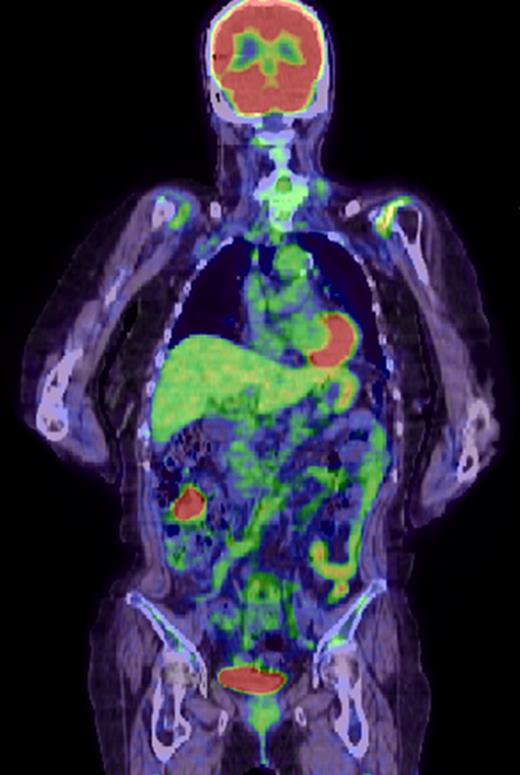

There was no evidence of tumor in the submandibular gland. Histological examination showed poorly differentiated SCC in the lymph nodes located at Level II (Fig. 1a). The patient was considered to have a carcinoma of unknown primary site because no primary lesions were found on detailed examinations of the esophagus, lung, uterine cervix and skin. A preoperative computed tomographic (CT) scan showed a small lesion with contrast effect in the transverse colon, which was difficult to distinguish from inflammation. Three months after operation, it was noted that the colonic lesion had grown considerably (Fig. 2). Fluorine-18 fluorodeoxyglucose positron emission tomography showed abnormal uptake in the transverse colon, but there was no accumulation at other sites (Fig. 3).

Fluorine-18 fluorodeoxyglucose positron emission tomographic scan shows positive findings in the transverse colon, with no other positive lesions.